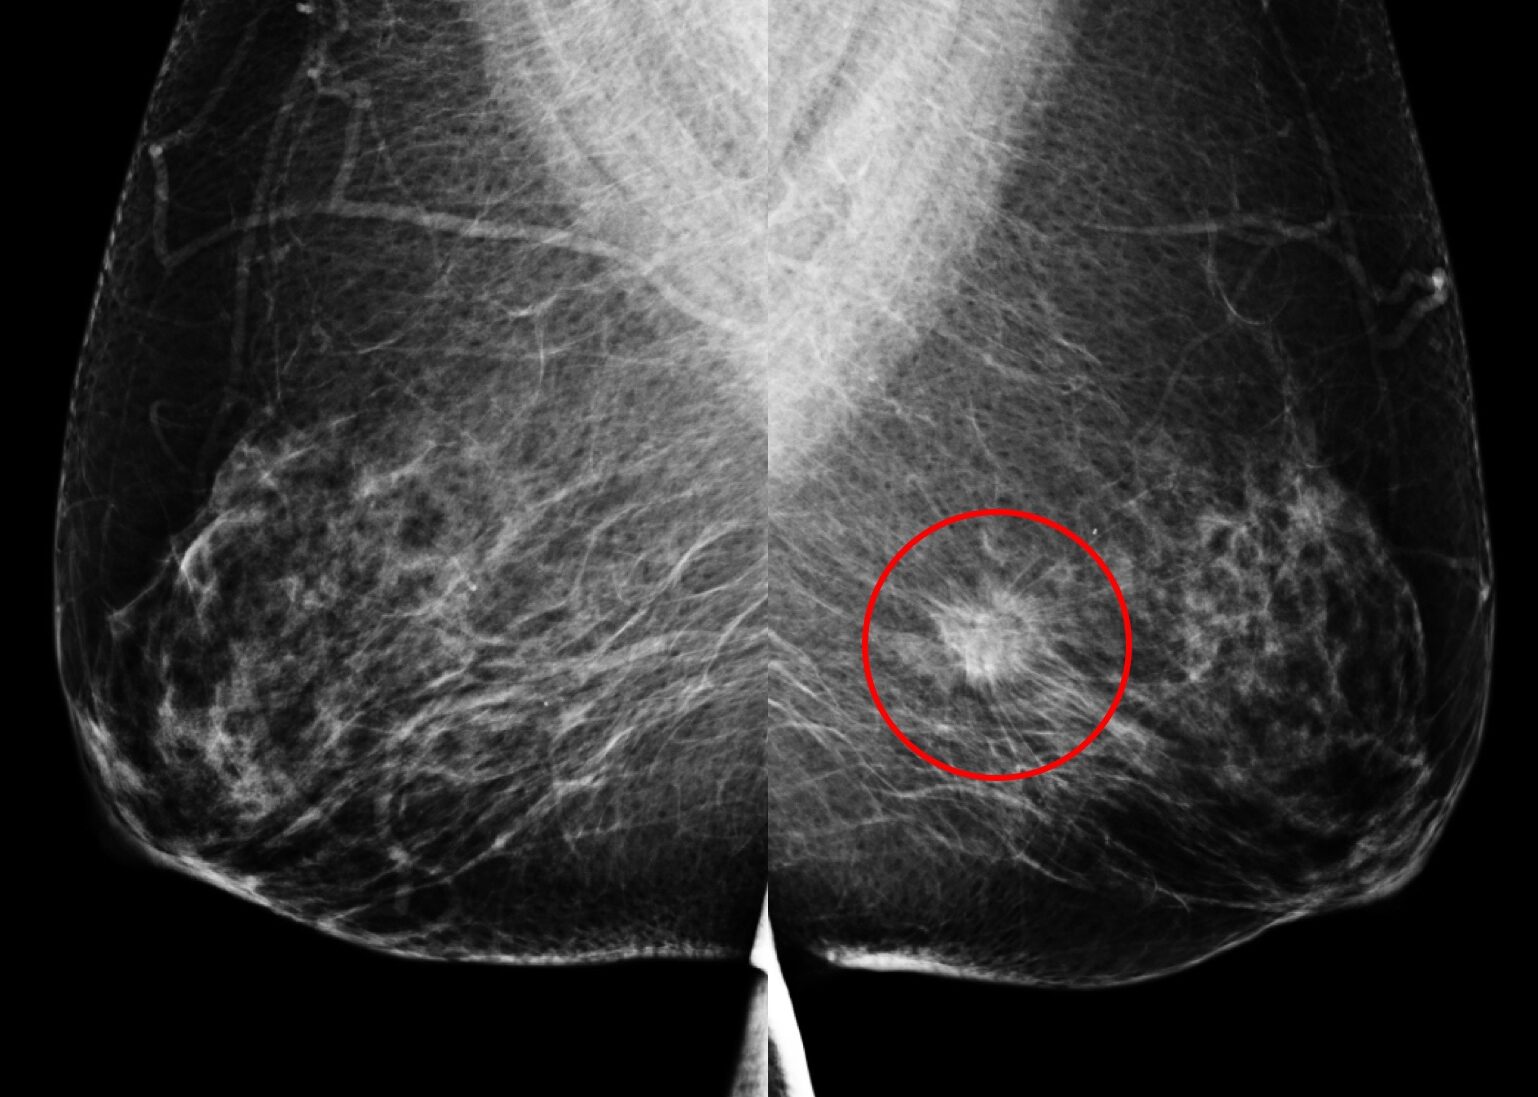

(A) 61歲女性於國健署「乳房攝影篩檢」發現:左乳上方有一不尋常的群聚鈣化點、經手術證實為乳房原位癌,後續恢復良好。

另一名55歲女性於國健署「乳房攝影篩檢」發現:左乳下方有一局部腫塊合併組織變形,經切片證實為早期乳房侵襲癌。

29歲女性,無生育史、無乳癌家族史。健康檢查經由「乳房超音波」發現:右乳內下側有一個14.8x6.2mm大小的不規則狀腫塊,經切片證實為乳癌,因早期發現而即時手術,恢復良好。